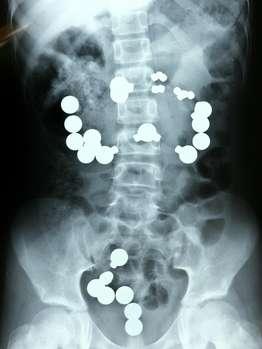

Magnetspielzeug geschluckt